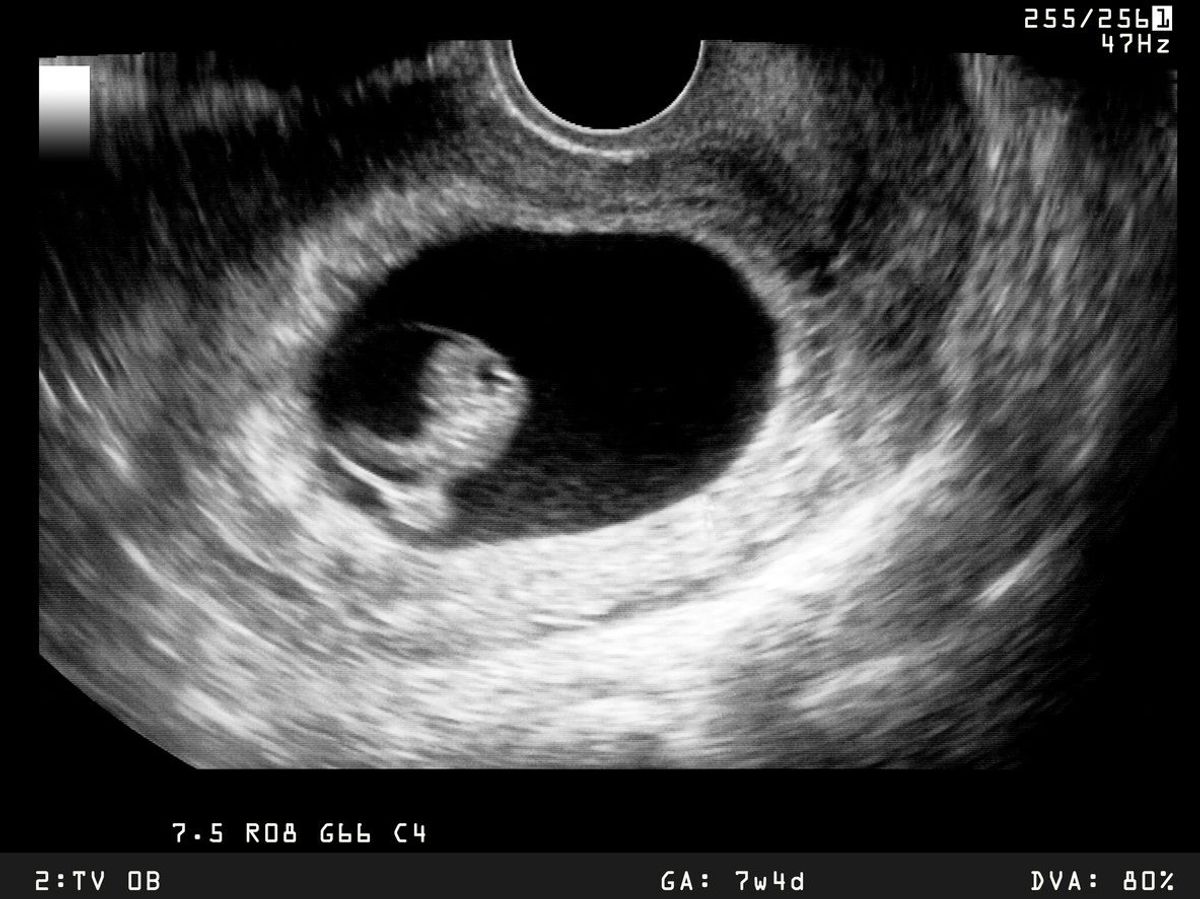

The embryo model, derived from pluripotent stem cells capable of differentiating into various cell types, exhibits a well-organised three-dimensional structure that closely resembles key developmental processes during the initial stages of human embryonic development, according to a study conducted at Cambridge University in the UK.

By allowing experimental modeling of embryonic development during the second week of pregnancy, these innovative models have the capacity to enhance our understanding of the origins of organs and specialised cells, including sperm and eggs.

The second week of pregnancy in humans is when the embryo implants into the uterus. However, this is also the time when many pregnancies are lost.

The new models derived from human stem cells do not have a brain or beating heart, but they include cells that would typically go on to form the embryo, placenta and yolk sac, and develop to form the precursors of germ cells, that will form sperm and eggs.

Many pregnancies fail at the point when these three types of cells orchestrate implantation into the uterus and begin to send mechanical and chemical signals to each other, which tell the embryo how to develop properly.